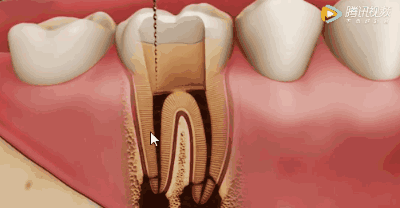

用银针锉去除牙髓

同时清洗移除牙髓残质及细菌。根管冲洗的目的是清除微生物、冲掉残渣,润滑根管器械和溶解有机残渣。然后,再进行根管消毒,使根管内达到无菌状态。